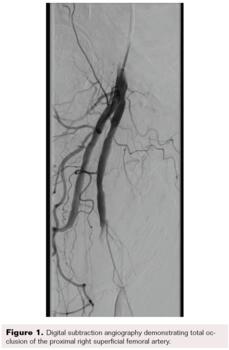

Maintaining an intraluminal course throughout, the SFA and popliteal arteries were successfully traversed using a stiff-angled Glidewire inside of a 0.035" Crosswalk braided peripheral microcatheter (Asahi Intecc Medical) for additional support. After advancing the microcatheter to the distal popliteal artery, the Glidewire was exchanged for a 0.014" pre-curved Mongo ES wire (Asahi Intecc Medical). The occluded anterior tibial artery was successfully navigated with the Mongo wire, after which intravascular ultrasound was performed from the anterior tibial artery proximally to the SFA. Next, laser atherectomy of the SFA, popliteal, and anterior tibial arteries was performed with a 1.7 mm Turbo-Elite laser atherectomy catheter (Philips) (Figure 3 and Figure 4). Following atherectomy, the anterior tibial artery was dilated with an Ultraverse 3.5 x 100 mm balloon (Bard). In preparation for percutaneous transluminal angioplasty of the SFA and popliteal arteries, the Mongo 0.014" wire was exchanged for a 0.035" stiff-angled Glidewire.

After the wire exchange, we attempted to aspirate, then flush, the 6F sheath with heparinized saline. After multiple failed attempts at sheath aspiration, we suspected a clotted arterial sheath and immediately proceeded to sheath exchange with a new 6F 45 cm sheath. Cautious to maintain wire position, the sheath was successfully exchanged. Saline flushing of the removed sheath resulted in expulsion of extensive clot burden (Figure 5). Repeat ACT confirmed therapeutic anticoagulation. The procedure concluded with percutaneous transluminal angioplasty followed by stenting of the SFA with BioMimics 6 x 150 mm stents (Figure 6). Final angiography demonstrated brisk flow through the SFA, popliteal, and anterior tibial arteries with no evidence of distal embolization (Figure 7 and Figure 8).